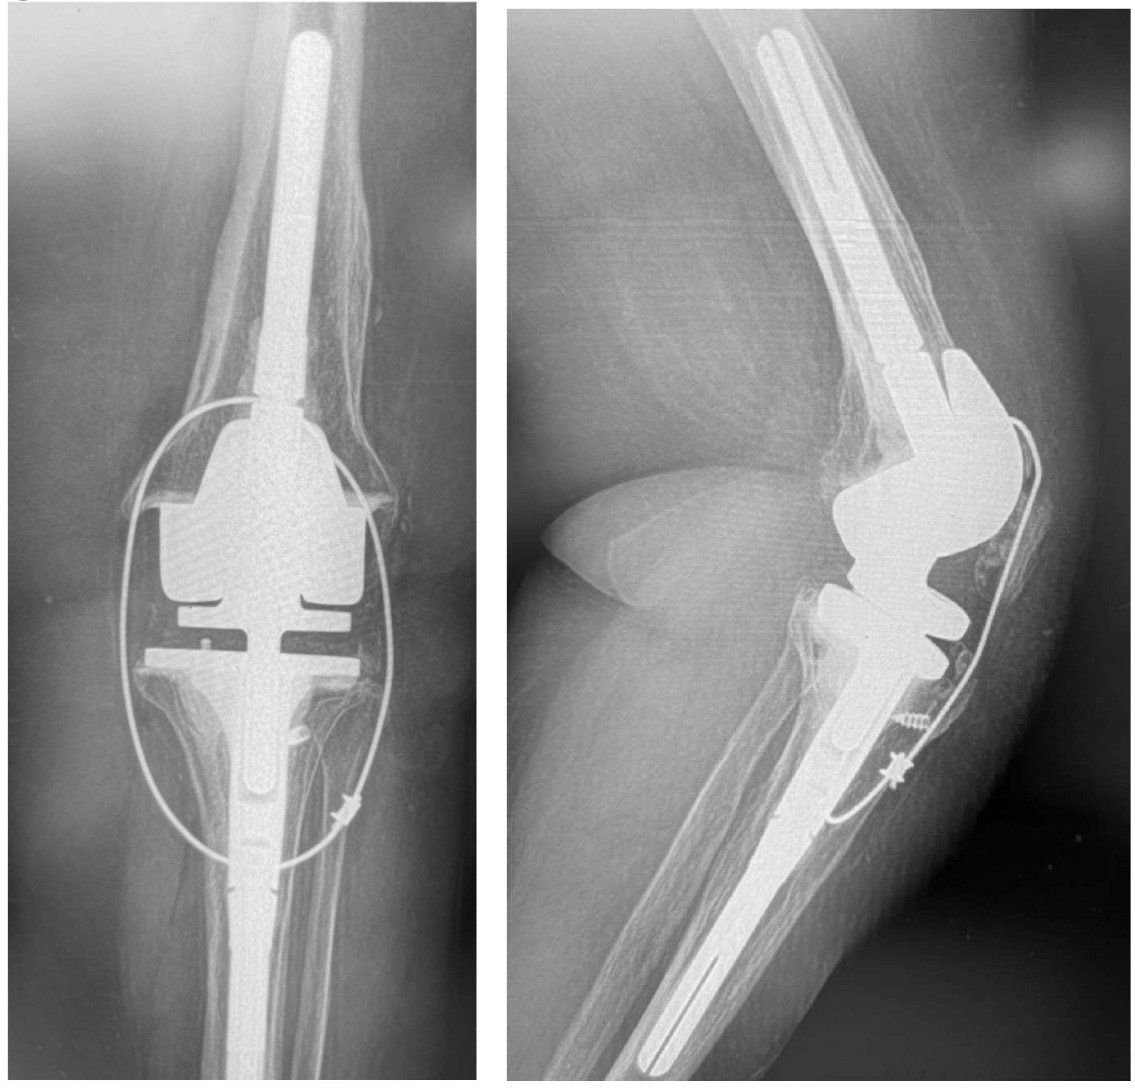

We removed the wire about six months following repair. At that time, she had ROM for 0-95 degrees. At six years out following repair she walks with no ambulatory aids and has full extension. (Figures 9, 10A-C)

Her recovery was uneventful and was “doing great!” In 2015 (2-years following repair), she requested that the cable removed. Unfortunately, in 2016, she fell again and re-ruptured her patellar tendon. The rotating hinge was retained in place and the patellar repair / protection technique performed. She was recently seen in September of 2025 (9.5 years post second repair) and reports full independent activities of daily living (ADL) without ambulatory aids. She has a slight “lag” and weakness, so I requested that she use a cain when outside. She has ROM through 104 degrees, but that is due to the mechanical limits built into the rotating hinge device.

She did mention that she could feel the cable “a little bit.” But urprisingly, when I offered to remove it, she said to leave it as is.

After about 45 cable repair protection procedures performed, only 25% have had their wires removed. They usually say, “it doesn’t bother me, so leave it alone, I don’t want to do it.” And they maintain full ADL without issues. In addition, most all patients achieve 104-120 degrees extension (104 due to their rotating hinge), and 5 degrees or less lag. Which is far better than the unprotected repairs in the literature. We are currently reviewing all out cases and will prepare an article for peer-review publication consideration.